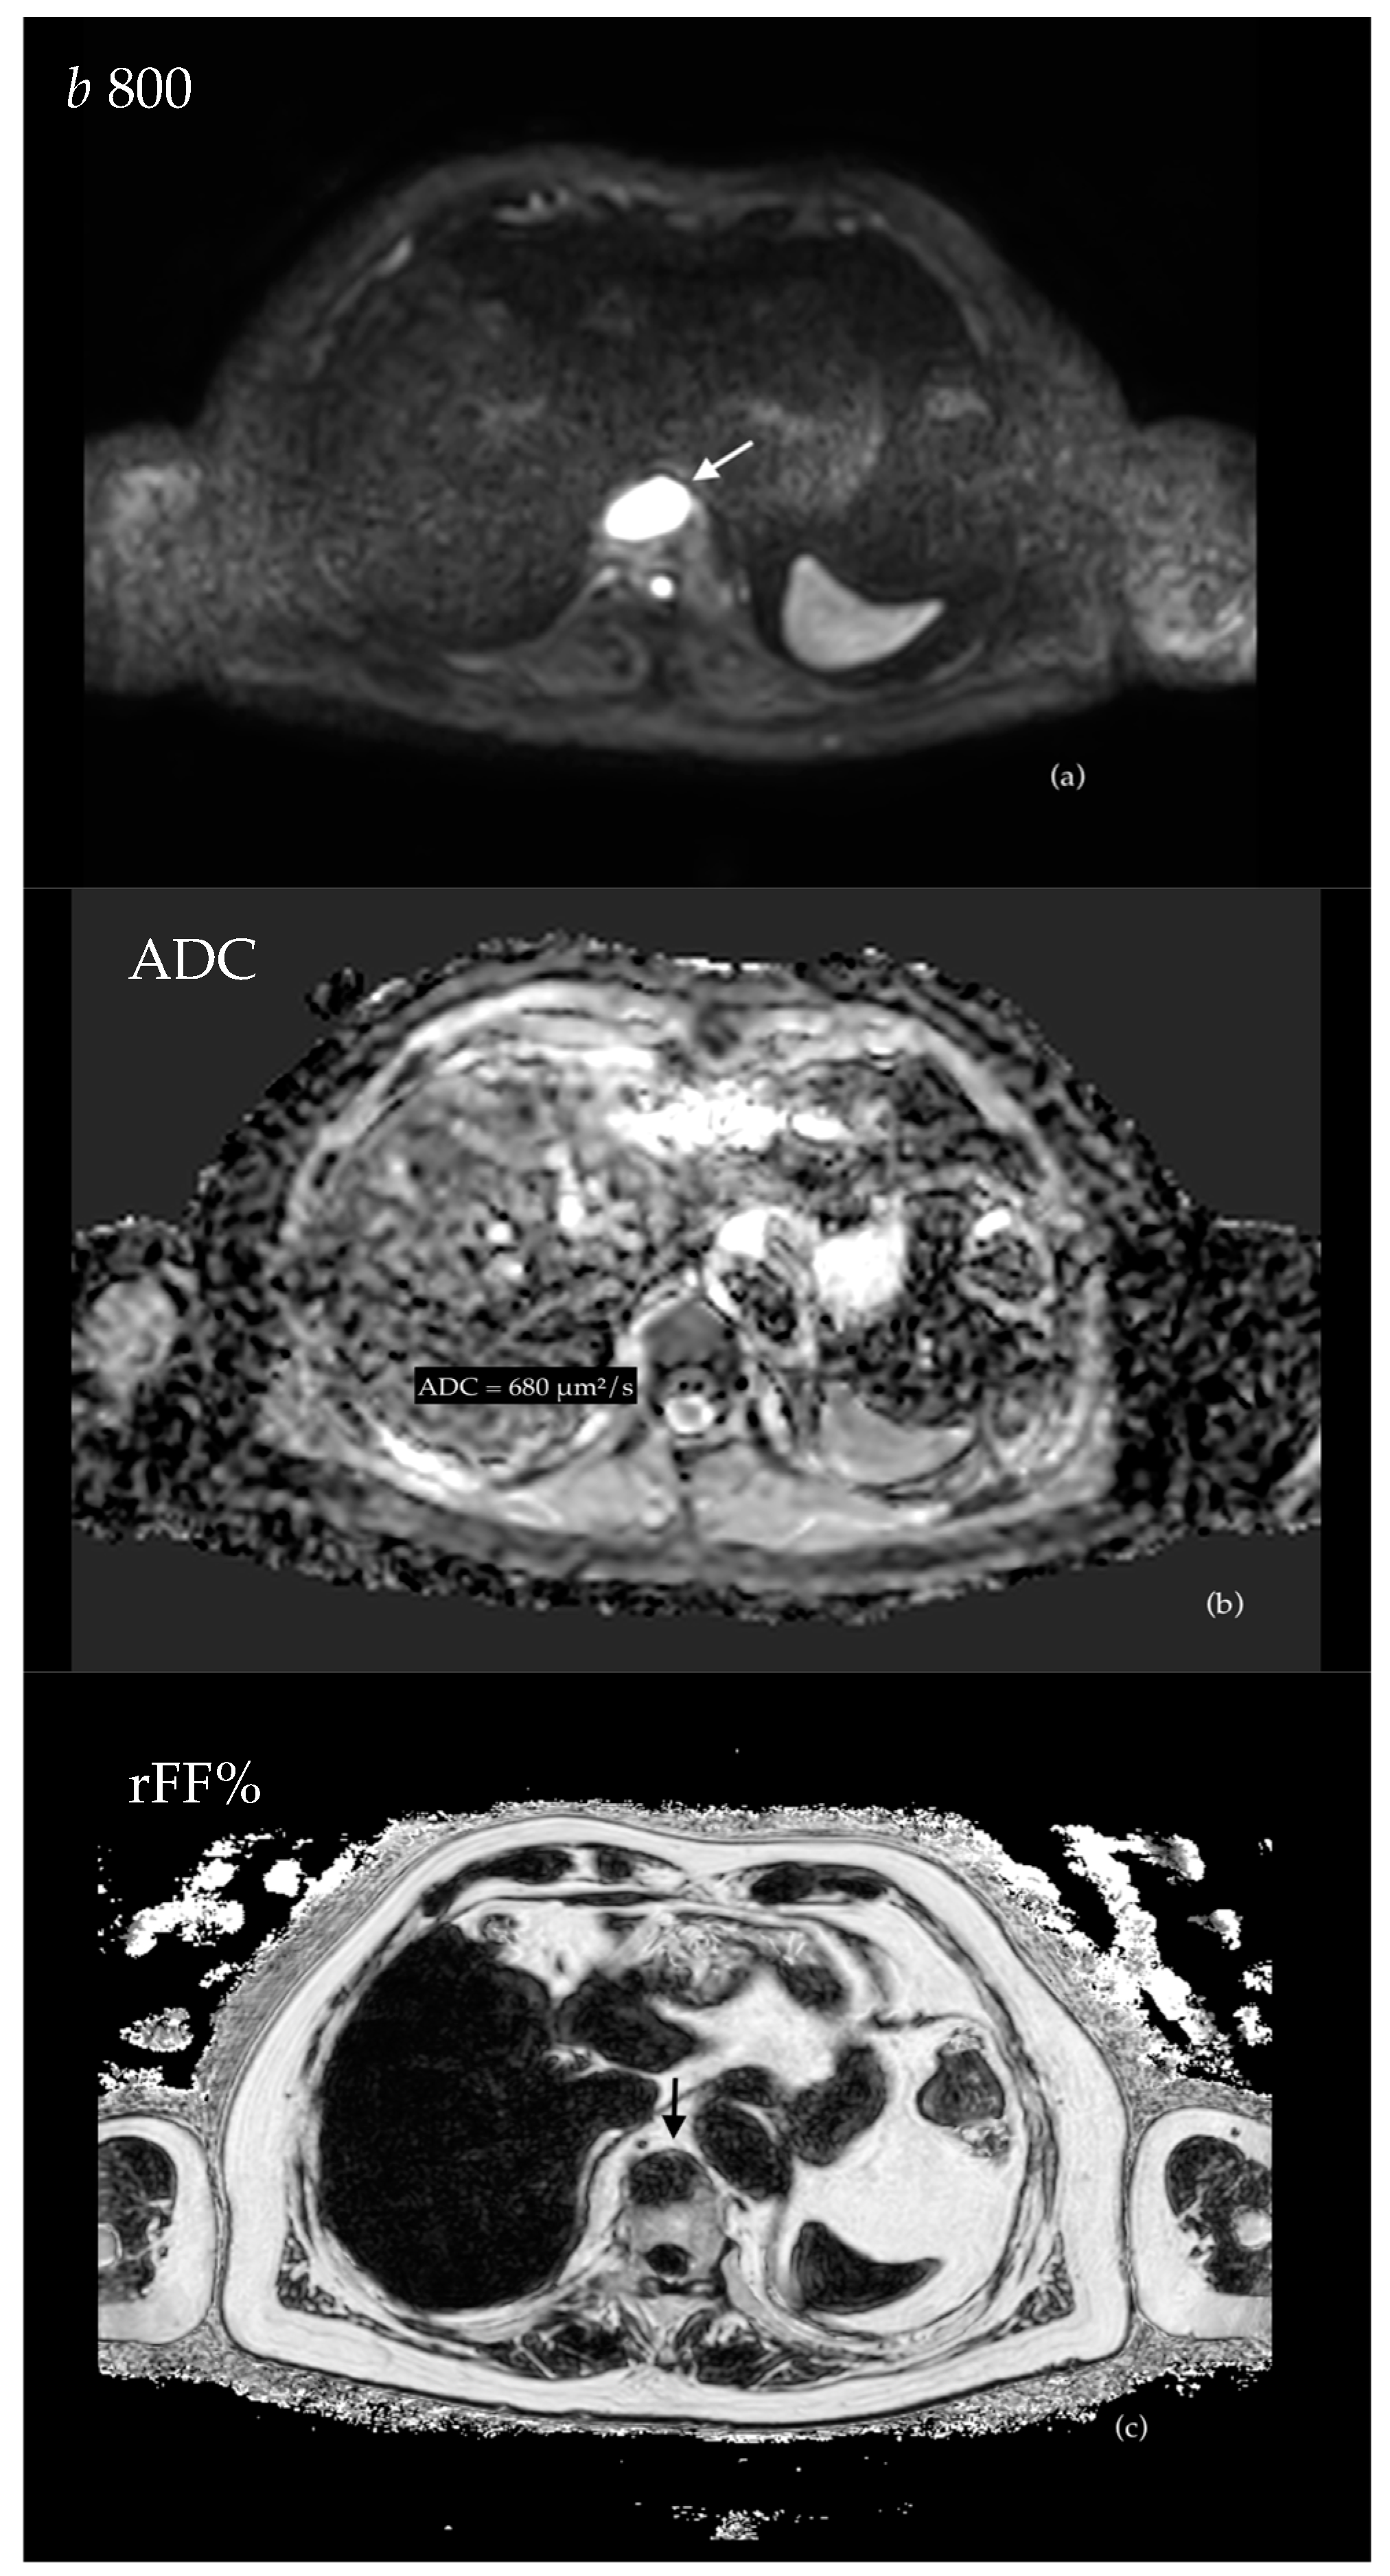

3.4.1. Evaluation of Bone Metastases with WB-MRI

3.5. Response Assessment in Metastatic Prostate Cancer

| Messiou et al. Eur Radiol 2011 [102] | Diffusion Weighted MRI | Overall ADC of bone lesions increases both in responders and progressors, but the magnitude of increase if higher for responders. An increase in overall ADC > 25% is 75% sensitive and 66.6% specific for response. ADC alone cannot confidently assess response or progression as the changes in bone marrow composition significantly influence ADC values. | |